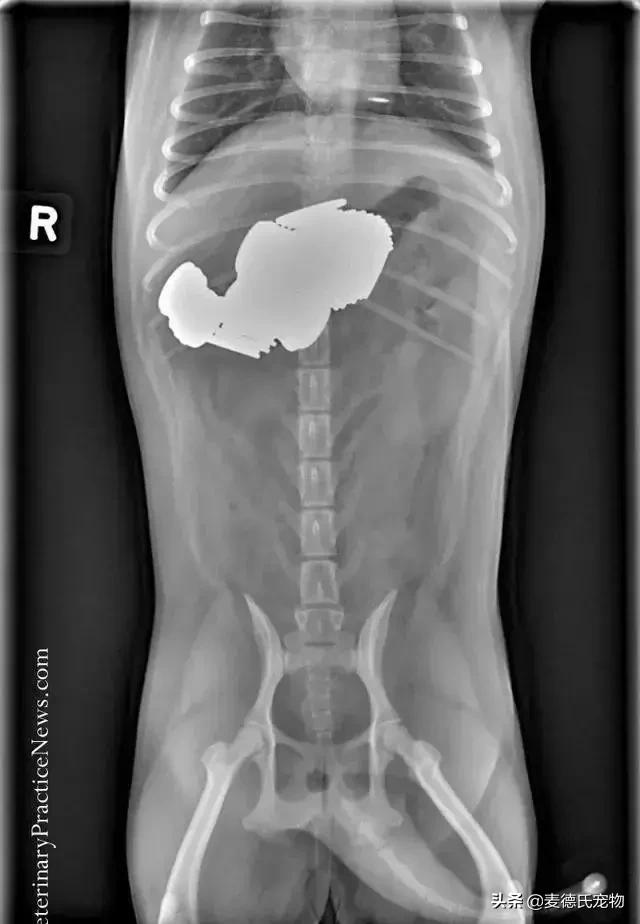

网友这才意识到情况的严重性,立马送Mortimer去了另外一家医院,在这里经过X光照射后,才终于发现了狗砸的病因——

它的胃部塞满了异物!

经过手术,医生一共从Mortimer胃里取出了19只婴儿安抚奶嘴!